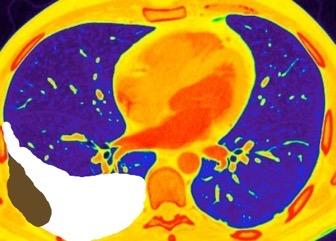

Carcinoma de mama con derrame pleural e implantes metastáticos

Makis W et al. Spectrum of Malignant Pleural and Pericardial Disease on FDG PET/CT. AJR. 2012